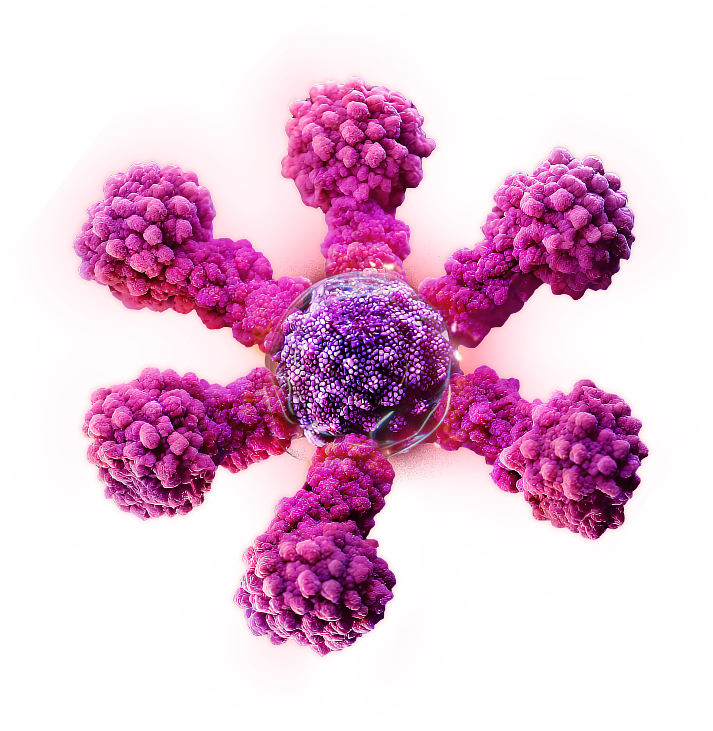

What is Protein-based Nanoparticle Technology?

Novavax’s protein-based nanoparticles are made of engineered proteins that help trigger an immune response.1

Presenting multiple copies of a protein on the surface of each nanoparticle helps to enhance the immune response, resulting in vaccines that may work better.1